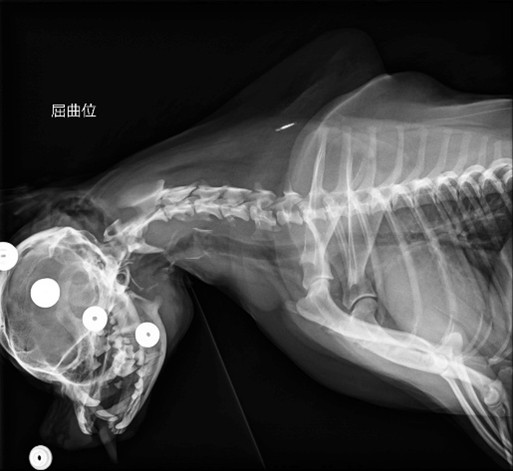

今回の症例は1歳10ヶ月のチワワちゃん。かかりつけの動物病院様で痛み止めを出されていましたが、四肢の硬直などがみられ、セカンドオピニオンで当院を受診されました。

レントゲン検査をしたところ、環椎と軸椎のずれが確認されました。普通にレントゲン撮るだけだと異常に気付きづらく、首を曲げて撮影したことで環軸亜脱臼疑いを発見することができました。